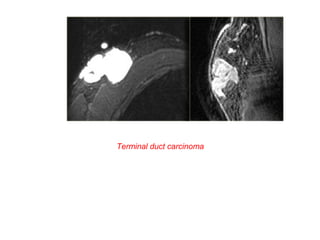

Two cases of intraductal carcinomas

Terminal duct carcinoma